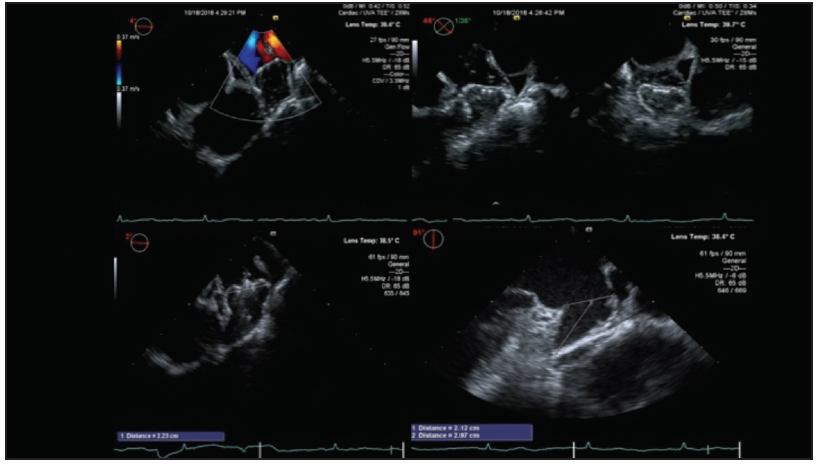

Figure 3. ICE probe manipulated in the left atrium to obtain views similar to those obtained using TEE.

A number of investigators have highlighted the utility of ICE for LAAO, with reported high efficacy and safety rates of 96.7% to 100%.36-39 Imaging can be accomplished from the right atrium, but only single-plane views can be achieved. Imaging can also be accomplished from the pulmonary artery, but with the same limitation of a single-plane view as well as the concern about manipulating the ICE probe through the right heart. Therefore, some investigators have proceeded to perform imaging from the left atrium, which can be accomplished via a single transseptal puncture (TSP) for both ICE and LAAO delivery systems (Figure 2). Once in the left atrium, the ICE probe can be manipulated to a series of positions (midleft atrium, anterior across the mitral valve, left upper pulmonary vein) to achieve views similar to that achieved by TEE multiplanes (Figure 3).

One of the concerns with such manipulations of the ICE probe in the left atrium is the risk of inadvertent injury, particularly in the thin-walled left upper pulmonary vein. Hence, a more recent advance is the utilization of 3D ICE, which obtains not only 3D reconstructed imaging (Figure 4 and Figure 5) but also, importantly, has the ability to do multiplanar reconstruction. All of these views by the 3D ICE probe can be achieved from a midleft atrial position, therefore obviating the need for aggressive probe manipulations in the left atrium and left pulmonary veins. A potential downside of the ICE probes remains their costs and impact on reimbursement.

Figure 4. Multiplanar reformatting can be used to align the LAA. Panel A shows a 45° view of the LAA and panel B corresponds to a 135° orthogonal view.

Figure 5. By rotating the green plane 45° counterclockwise, we obtain the 0° and 90° views (A, B).